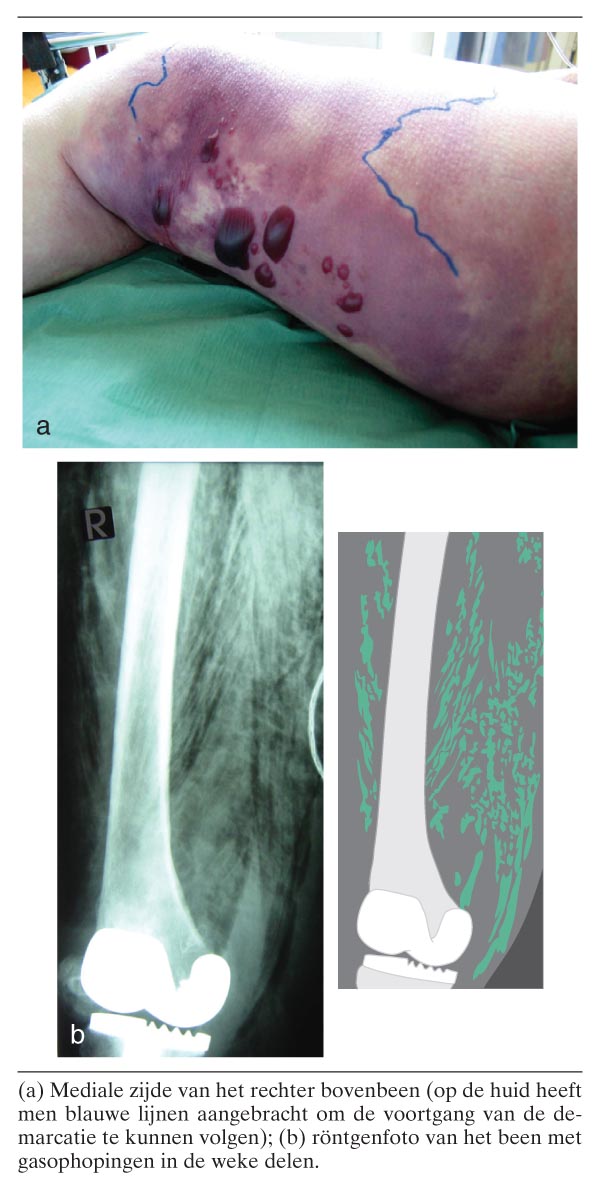

Een 80-jarige vrouw werd opgenomen wegens pijn in het rechter bovenbeen, hypotensie en kortademigheid. Haar voorgeschiedenis vermeldde een knieprothese, myelodysplastisch syndroom, depressiviteit en recentelijk buikklachten. Het bovenbeen was gezwollen en toonde een scherp afgrensbare, blauwpaarse verkleuring met grote hemorragische bullae (figuur a). Een röntgenfoto toonde gasconfiguraties onder de huid en tussen de spieren (zie figuur b). Een grampreparaat van het blaarvocht toonde grampositieve staafjes, die later als Clostridium septicum werden gedetermineerd. De behandeling bestond uit vloeistofresuscitatie, mechanische beademing, inotropica en antibiotica. Wegens de onderliggende ziekten, de diepe septische shock met multiorgaanfalen en de uitgebreidheid van een…